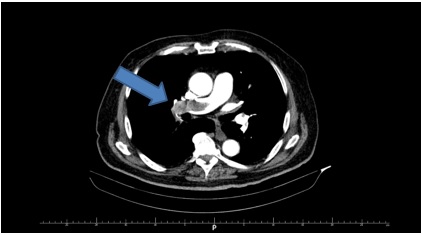

Strzałka wskazuje: